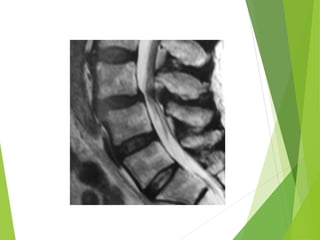

 Muestran una hidromielografía de la columna lumbar con

espondilolistesis L4 y discartrosis L5 severa que condicionan un

canal lumbar estrecho.

Discopatías con protrusiones discales y osteofitos

evidenciados por la Mielografía